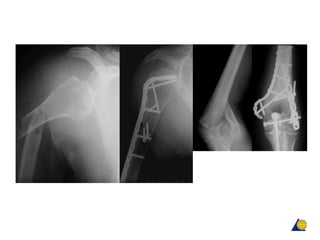

Humeral shaft fractures—retrograde IM

nailing

• Interlocked nails may also be inserted through distal site

• Care to avoid fracture at entrance site

Humeral shaft fractures—locked IM nails

Design modifications to avoid

shoulder problems:

• More lateral entrance site

• Retrograde insertion